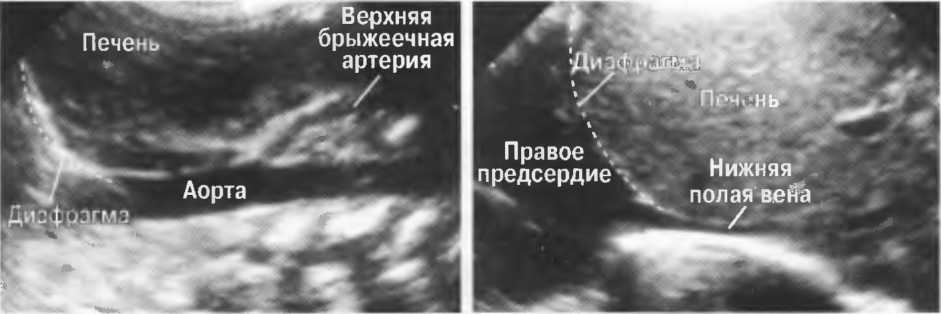

2. Верхняя брыжеечная артерия должна визуализироваться в виде округлого или овального эхонегативного образования, расположенного рядом с поджелудочной железой у здорового взрослого обследуемого (рис. 24). Наиболее простым способом проверки качества изображения является визуализация своей собственной верхней брыжеечной артерии. Сохраняйте эхограммы после каждого исследования для сравнения.

Рис.24. Поперечный срез: верхняя брыжеечная артерия представлена эхонегативным округлым образованием, окруженным эхогенной жировой клетчаткой, расположенным близко к поджелудочной железе.